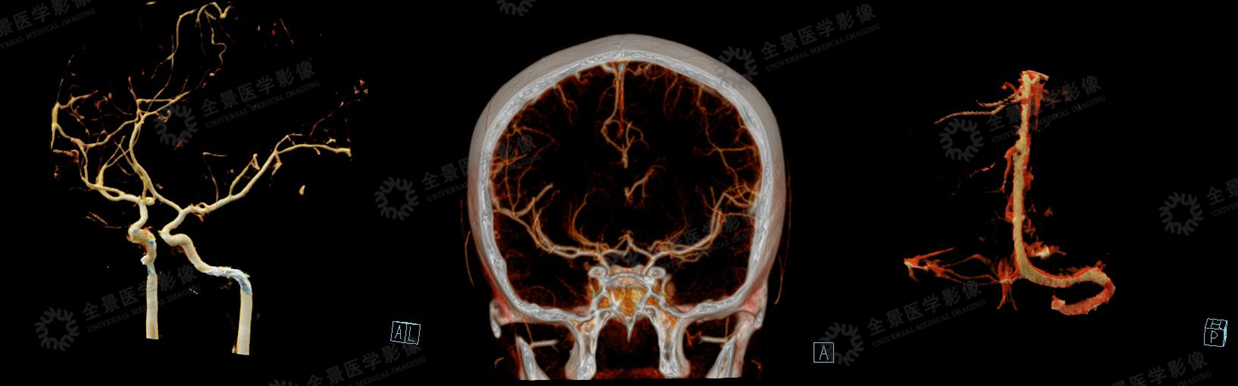

右侧额叶、基底节与对侧比较,CBF下降明显,CBV无明显差异,

MTT、TTD时间明显延长。(前循环供血范围)

CTA示:右侧颈内动脉闭塞,颅内血管多发粥样硬化。

CTV示:静脉未见明显异常。

右侧颞叶与左侧比较,CBF稍增加,CBV无明显差异,MTT、TTD时间稍延长。

通过多期的血管重建,发现右侧颞叶附近有明显的侧枝循环建立。